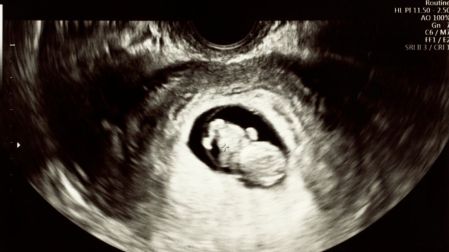

Hormonas inmunoprotectoras en el embarazo: así protege el cuerpo al bebé

Progesterona, prolactina y vitamina D ayudan a que el sistema inmune tolere al feto y proteja la salud de la madre durante el embarazo.

Durante el embarazo, el organismo femenino no solo sostiene y desarrolla una nueva vida, sino que también realiza ajustes complejos para proteger al bebé sin comprometer la salud de la madre.